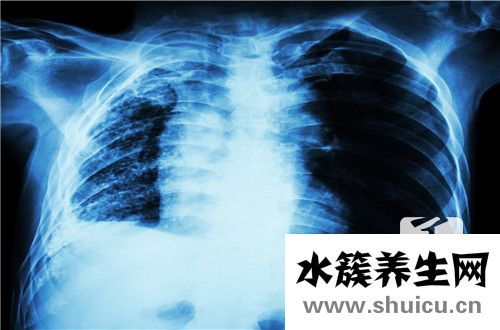

鈣化是組織修復的一種手段,不需要治療,也不會傳染。一般來說,對身體沒有太大影響。在多數情況下;肺癌的鈣化斑點僅是人肝細胞壞死后的一些特殊變異。人體每天都在代謝。一些細胞壞死是正常現象。壞死后,由于肺部自身循環暢通,肺部變得平靜。在胸部X光片中形成的鈣化斑點非常像石頭的亮點。一般來說,這些斑點在胸片上僅約0.5cm。鈣化斑點,如皮膚上的長痣,只是一些壞死細胞的平靜,大多是良性,部分結核性鈣化,大多數患者本身沒有癥狀,一般不需要處理它們。

鈣化意味著當疾病治愈時,當人體組織壞死或患有腫瘤時,鈣鹽沉積在此處形成鈣化灶。在X射線或CT下,鈣化斑點通常高于骨密度,顯示出高骨密度信號。在人體衰老過程中,鈣鹽在肋軟骨沉積中的高密度影像表現,一般左右對稱密度高于骨,如果不是應該考慮病理變化。